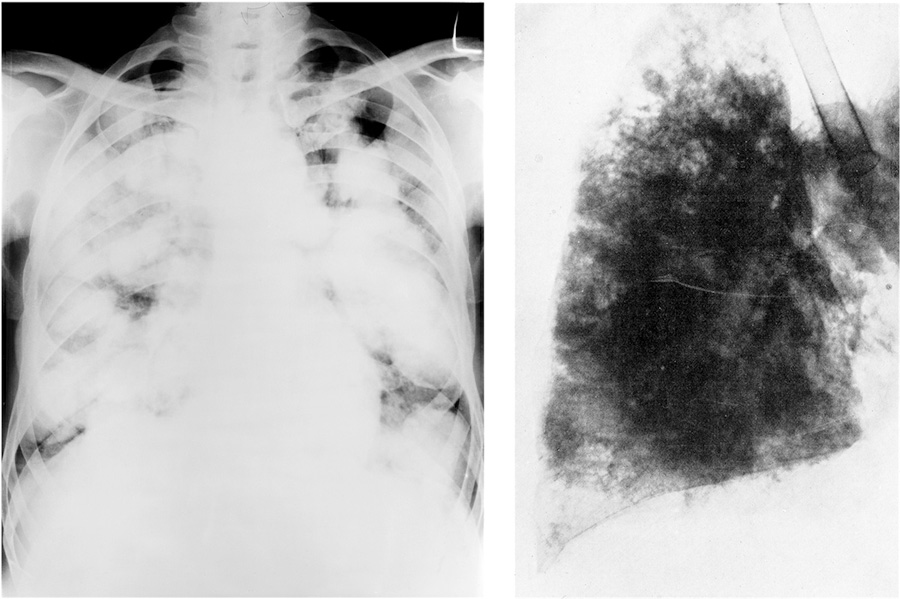

I.1. Слева: Рентгенография грудной клетки, демонстрирующая туберкулез. Справа: Фотография легких пациента после смерти от туберкулеза (1903)